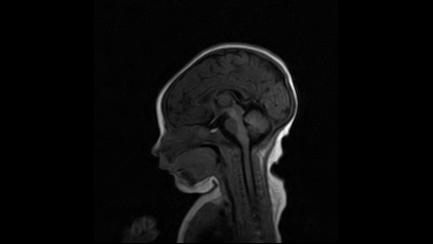

标题: PED3413:患儿女6天体检

缺血缺氧性脑病

6天为新生儿,髓鞘发育正常;左侧颞顶叶蛛网膜下腔增宽,请结合临床。

1。缺血缺氧性脑病2。左侧颞顶叶外部性脑积水,可观察

半卵圆中心上方层上可见对和乐大脑皮质t1高信号,考虑有hie可能,不知有何症状,建议加做dwi及复查

符合缺氧缺血性脑病影像表现。